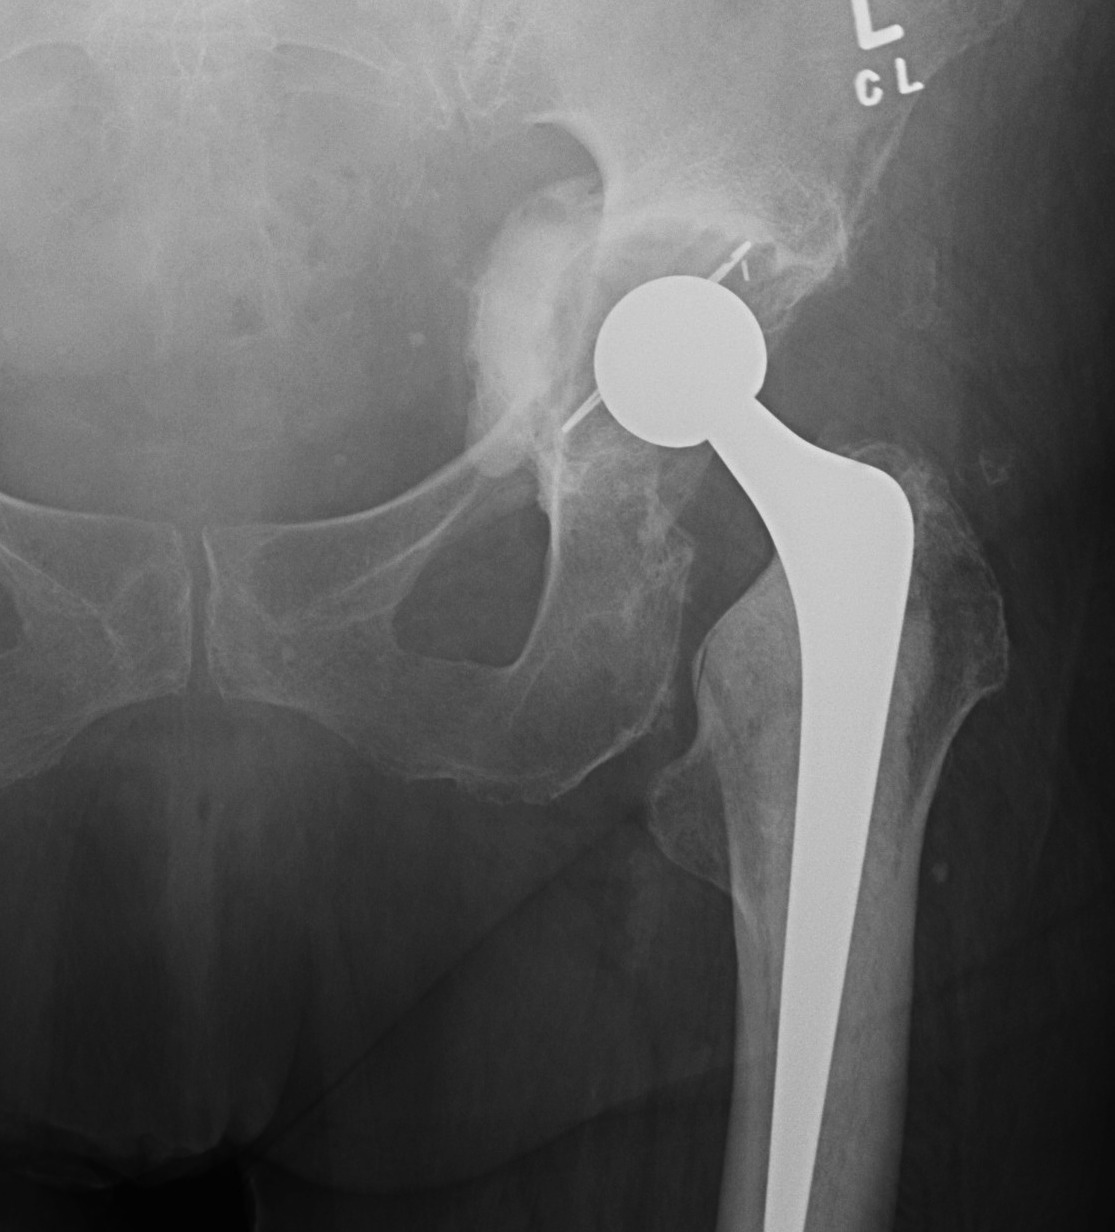

Acetabulum Removal

Acetabular revision only

1. Leave femoral component in situ

Indications

- femur not loose / damaged / good orientation

- need to be able to match new cup / poly to femoral head

Uncemented Acetabulum

Options

- may just be changing liner and leaving cup

- may need to remove well fixed cup i.e. infection

- may be removing loose cup

Metal Shell

1. Curved osteotomes

- risk bone loss

2. Zimmer Explant Acetabular Removal System

- 3 sizes depending on implant size

- central head to sit in liner

- must remove screws first, then replace liner

- diamond blades cut between cup and bone

- initial blade short

- second is thin and full radius